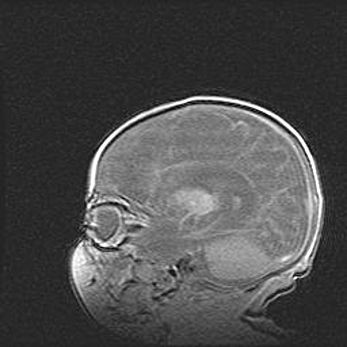

Подострая гематома правой гемисферы мозжечка.

Наружная гидроцефалия.

Возраст: 15 дней

Вес: 3100 г

Пол: женский

Окружность головы: 37 см

Срок гестации: 35-36 недель

При открытой наружной форме гидроцефалии у новорожденных расширяются и переполняются субарахноидные пространства.

Кровоизлияния в мозжечок имеют две клинико-анатомические формы: полушарные гематомы и кровоизлияния в червь.

К появлению этой патологии может привести: повреждения головного мозга, возникающие в результате асфиксии и гипоксии плода при беременности, или травмы во время родов. Редко гематома мозжечка может быть результатом первичной коагулопатии и сосудистой мальформации, диссеминированном внутрисосудистом свертывании, изоиммунной тромбоцитопении.